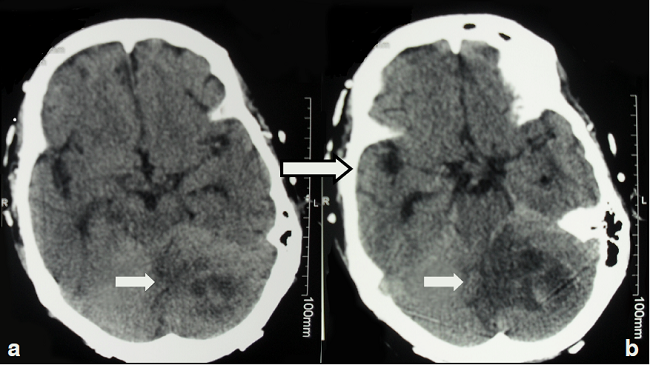

A partir de esa fecha, incluso cuando todavía estaba bajo tratamiento inmunosupresor, el paciente comenzó a presentar fiebre intermitente, cefalea persistente, insomnio, vértigo y agitación psicomotora. Se le practicó una tomografía cerebral, la cual evidenció una lesión de 36 x 43 mm que ocupaba espacio en el hemisferio cerebeloso izquierdo y sugería la presencia de un absceso cerebral (figura 1).

La resonancia magnética de control demostró que la resección había sido completa, con una zona de encefalomalacia residual. Con base en el diagnóstico histológico, se decidió suspender el tratamiento antibiótico y continuar con la administración de anfotericina B liposómica durante dos semanas y, posteriormente, con 200 mg de voriconazol oral cada 12 horas durante 12 meses, obteniéndose una evolución adecuada.